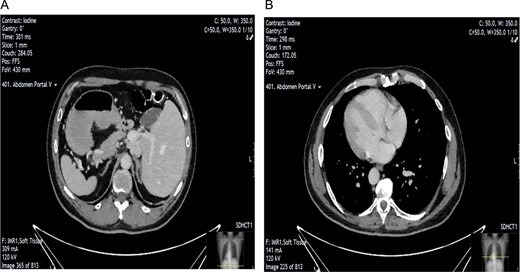

A 54-year-old man, known to have SIT, was referred to the general surgical unit with epigastric pain, dysphagia, and weight loss. Initial investigation with upper GI endoscopy was technically difficult and raised the suspicion of gastric volvulus. A CT scan of the abdomen and pelvis was subsequently carried out (Fig. 1). This showed SIT and mild nodularity of the gallbladder wall, thought to represent a 7.1 mm gallbladder polyp. Given the patient’s symptoms, the decision was made to perform an LC [6].

CT scan showing evidence of SIT. Image A shows position of gallbladder and evidence of nodularity. Image B showing dextrocardia indicative of SIT.